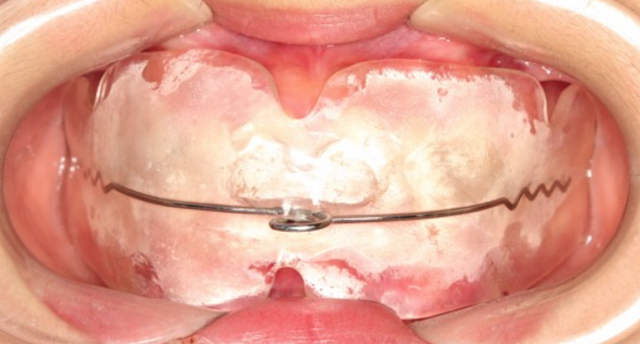

第三,如果已經發(fā)生了口腔錯合畸形,就需要根據不同的錯合畸形類型進行功能性矯正和后期的固定矯正了。